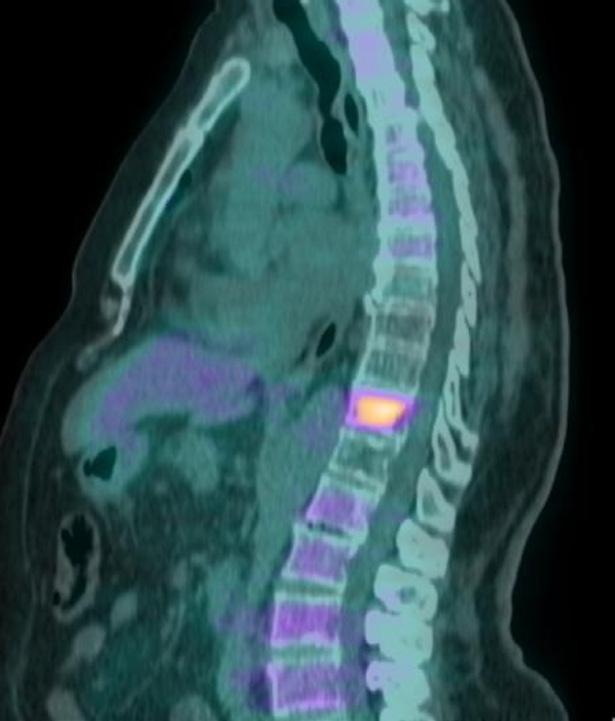

Alla PET di Novembre 2021 (figura 4) si evidenzia ulteriore PD scheletrica su D9 e osso sacro per cui dal 17/12/2021 al 04/01/2022 è stata sottoposta a trattamento RT i salvataggio su (D9- Sacro ) con tecnica 30 Gy. La paziente prosegue con il doppio blocco fino al mese di Luglio 2022 (56° ciclo di pertuzumab e trastuzumab).

Figura 4. PET Novembre 2021.